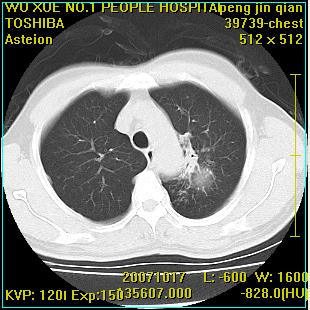

标题: CT10148:男,56岁,咳血。 [打印本页]

标题: CT10148:男,56岁,咳血。

左肺上叶尖后段较大团块影,边缘光滑,内见不规则裂隙样空洞,周围明显见细小结节及渗出,与肺门方向结构紊乱,另:左上叶尖段外侧 舌叶内侧 右上叶尖段及下叶背段均见片状致密影。考虑:继发性肺结核伴空洞形成!

左肺上叶尖后段较大团块影,边缘光滑,内见不规则裂隙样空洞,周围明显见细小结节及渗出,与肺门方向结构紊乱,另:左上叶尖段外侧 舌叶内侧 右上叶尖段及下叶背段均见片状致密影。考虑:继发性肺结核伴空洞形成!建议进一步检查,除外肺癌

以下是引用卜一在2007-10-22 16:36:00的发言:[br]左肺上叶尖后段较大团块影,边缘光滑,内见不规则裂隙样空洞,周围明显见细小结节及渗出,与肺门方向结构紊乱,另:左上叶尖段外侧 舌叶内侧 右上叶尖段及下叶背段均见片状致密影。上腔静脉后淋巴结肿大,内有钙化。考虑:继发性肺结核伴空洞形成!

浸润型肺结核伴左上肺空洞形成,两肺播散灶